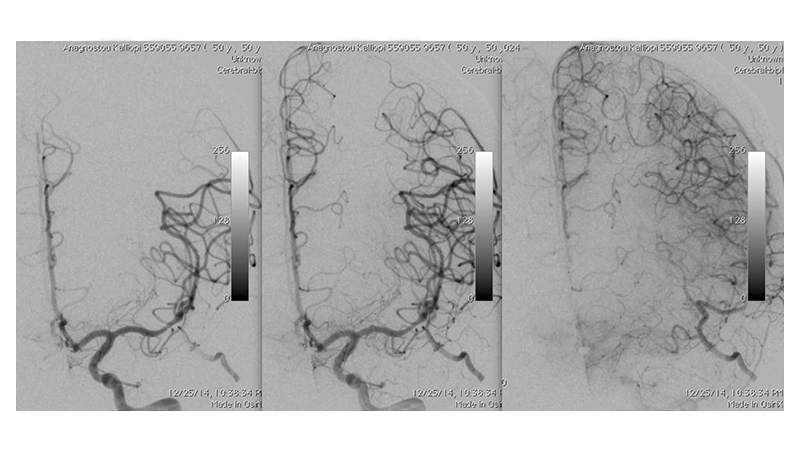

Εικόνα 4: Διέλευση με μικροκαθετήρα της αποφράξεως και τοποθέτηση του μικροκαθετήρα στο βάθος του Μ2.

Εικόνα 5: Έκπτυξη stent retriever κατά μήκος του αποφράσσοντος θρόμβου.

Εικόνα 6, 7: πλήρης αποκατάσταση της ροής και επανακαναλοποίηση της μέσης εγκεφαλικής αρτηρίας μέσα σε 20 λεπτά, χωρίς κλινικές επιπτώσεις.